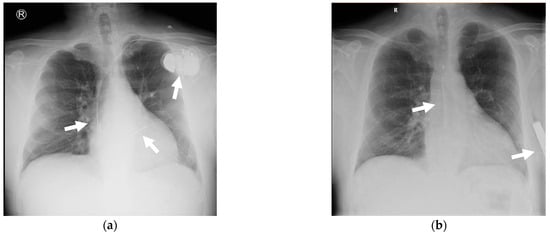

After three months, to reduce the risk of recurrent CIED-IE and in the absence of indication for cardiac resynchronization therapy or pacing, an S-ICD was implanted (Figure 7). The timing of the S-ICD implantation was not based on immediate medical necessity, but rather on the availability of resources, as S-ICD is a relatively new therapy, and its use was contingent on its accessibility at the time.

Figure 7. Chest X-ray: (a) on the left side (at admission), a bicameral ICD is visible, with arrows indicating the generator located in the left subclavicular region, the leads situated in the right atrium and right ventricle, respectively. On the right side (b) after S-ICD implantation, the chest X-ray shows arrows indicating the S-ICD electrode and the S-ICD generator.